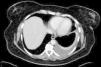

Clásicamente se había sugerido que la presencia de colesterol en el espacio pleural se debía a la degradación de eritrocitos y neutrófilos en el interior de una pleura engrosada, pero su origen parece derivar de las lipoproteínas séricas más que de la lisis celular1. El engrosamiento pleural con tejido cicatricial fibrótico que dificultaba la absorción del líquido era considerado un aspecto clave en la etiopatogenia del seudoquilotórax1. Sin embargo, en los últimos años se ha señalado la existencia de algunos casos de seudoquilotórax en pacientes con artritis reumatoide en los que no existe engrosamiento pleural, poniendo en duda el mecanismo patogénico habitualmente aceptado4,5. Hemos diagnosticado un nuevo caso de seudoquilotórax en una paciente con artritis reumatoide, en la que no existía engrosamiento pleural. Una paciente de 53 años fue remitida a neumología por el hallazgo de un derrame pleural de escaso volumen, sin síntomas asociados, detectado en el estudio preoperatorio de eventración abdominal. La paciente disponía de una radiografía de tórax realizada 7 meses antes, sin derrame pleural. Era fumadora de 25 paquetes-años, sin síntomas respiratorios previos. Estaba diagnosticada de artritis reumatoide desde 2 años antes, en tratamiento con corticoides, metotrexato y certolizumab. En la TAC de tórax (fig. 1) se apreciaba un derrame pleural sin signos de engrosamiento pleural. Se realizó una toracocentesis con obtención de líquido opalescente, sin gérmenes, ni células malignas, con pH 7,03, glucosa <20mg/dl, proteínas 7g/dl, LDH 14.691U/l, ADA 137U/l, factor reumatoide <9U/ml, triglicéridos 17mg/dl y colesterol 255mg/dl (sérico 186mg/dl).